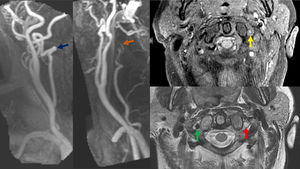

Registro video Head Impulse Test (vHIT) de ambos canales semicirculares laterales durante el primer día de ingreso. Clínicamente la paciente presentaba un síndrome vestibular agudo aislado. Los resultados demuestran bilateralmente la presencia de ganancias medias normales del reflejo vestíbulo-ocular (0,97 en lado izquierdo y 0,99 en lado derecho, (*) así como la ausencia de sacadas de refijación (flechas negras).